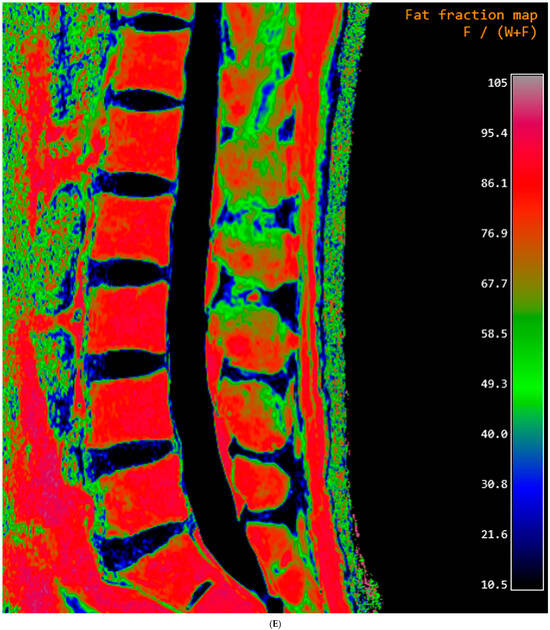

The FF measurement was independently performed by two radiologists who were unaware of the clinical information. Firstly, the FF measurements in GRE-based CSE-MRI were conducted using the INFINITT picture archiving and communication system. Elliptical regions of interest (ROIs) were drawn on the FF map, excluding the posterior venous complex and cortical bone, to encompass cancellous bone as much as possible (Figure 1). ROIs were delineated to the mid-sagittal image. In cases where obtaining information from the central image was challenging, ROIs were drawn on parasagittal images. Measurements were conducted on the L1–L4 bodies, and, in cases where abnormalities invaded all sagittal slices, this level was excluded from the measurements. The median values of the measurements were utilized as representative values (FFGRE). Next, the FF measurement in SE-based CSE-MRI was determined using diffusion analysis software (EXPRESS version 1.0, Philips Healthcare, Seoul, Republic of Korea). This program generates a fat fraction map by simply dividing the signal from the fat-only image by the sum of the signals from the water-only and fat-only images. After creating the FF map using mDixon-XD images, using the same criteria and methodology as in GRE-based CSE-MRI measurements, FF values were obtained from L1–L4 bodies (Figure 1), and the median was used as the representative value (FFSE).

Figure 1.

Lumbar spine MRI of a 59-year-old male. (A) Fat fraction (FF) measurement on gradient-echo (GRE)-based chemical-shift-encoded magnetic resonance imaging (CSE-MRI). The FFGRE in this patient was 66.91%, representing the median value of the L1–L4 vertebral bodies. (B) FF measurement on spin-echo (SE)-based CSE-MRI. The FFSE was 85.84%. The numbers in the figure indicate the ROI numbering in the EXPRESS program. (C) Measurement of the vertebral bone quality (VBQ) score was calculated by dividing the median value of T1-weighted signal of L1–L4 vertebral bodies by the cerebrospinal fluid (CSF) signal at the L3 level. The VBQ score for this patient was 2.63. (D,E) FF color maps were created through GRE- and SE-based CSE-MRI.